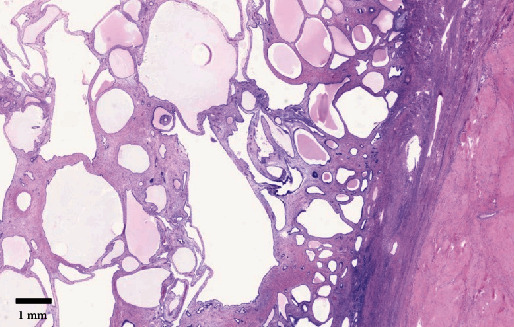

子宫内膜息肉是子宫内膜腺体和基质在子宫腔内无序生长的良性肿瘤。它们与不孕症、异常子宫出血和使用他莫昔芬有关。虽然大多数息肉的大小小于 2 厘米,但罕见的巨大息肉会引起恶性肿瘤的担忧。我们报告了一例 58 岁女性的 15 厘米巨大子宫内膜息肉病例,该女性有服用他莫昔芬的病史,并以便秘为常见主诉。此外,我们还对巨型子宫内膜息肉病例进行了文献综述。该病例是迄今为止报告的最大的子宫内膜息肉。

Endometrial polyps are benign disorganized growth of endometrial glands and stroma in the uterine cavity. They are associated with subfertility, abnormal uterine bleeding, and tamoxifen use. While most polyps are smaller than 2 cm in size, rare giant polyps can cause concerns over malignancy. We report a case of a 15 cm giant endometrial polyp in a 58-year-old woman with a history of tamoxifen use who presented with an uncommon complaint of constipation. Additionally, a literature review of giant endometrial polyp cases is presented. This case represents the largest reported endometrial polyp to date.